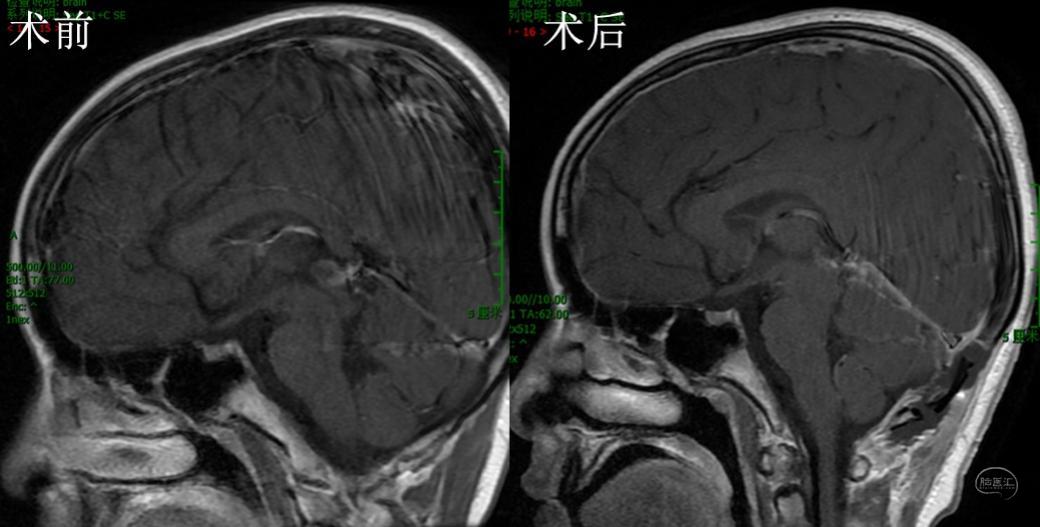

完善术前检查后,在全麻下行内镜下经幕下小脑上入路切除松果体区囊肿。俯卧位,枕下正中切口,骨窗充分暴露窦汇和双侧横窦。剪开、悬吊硬膜,经幕下小脑上探查松果体区,见囊肿位于第三脑室后部,锐性分离周围缘蛛网膜,完整切除囊肿,第三脑室结构清晰可见,保护完好(附视频)。术后MRI示囊肿消失(图2)。患儿恢复良好,无后遗症,1周出院。

图2,术后MRI检查,A、B、C分别为冠矢轴位手术前后增强MRI